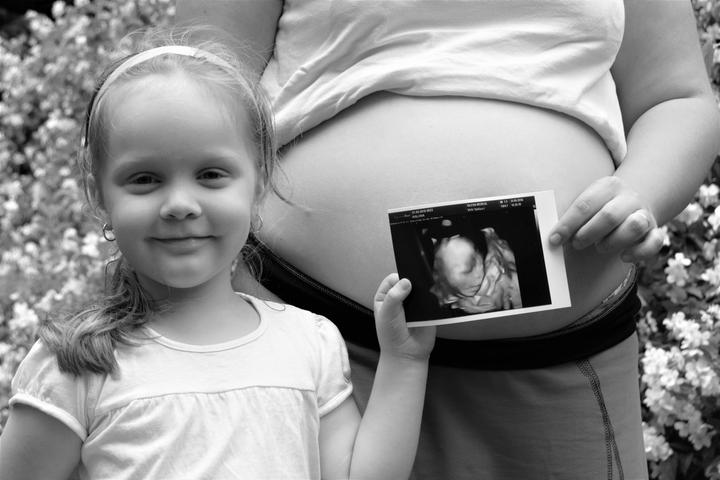

Tento článek je o možnosti informovat o mé dceři Štěpánce, která úžasne, hrdě a statečně bojuje proti nepřízni osudu. Tak tedy tady je její příběh.

Štěpánka se narodila 16.10.2014 s několika diagnózami, které ve vzájemné kombinaci výrazně ovlivňují vývoj a budoucnost. Hydrocephalus, Těžká centrální hypotonie, Genetická nebalacovaná chromosomální přestavba, Hypermobilita,Sinus pilonidalis, sluchová porucha, oční vada, epilepsie.Lékaří již od začátku ke Štěpánce přistupovali s odsouzením k těm nejhorším představám o budoucnosti. Ale i přes jejich prognózy se s tím Štěpánka pere a zatím i když po malých krůčkách jejich prognózy boří a neustále překvapuje. Nyní však potřebuje pomoc i okolí a ta je bohužel velmi finančně náročná.

V současnosti nesedí, nemluví, neleze, nechodí a učí se přijímat potravu lžičkou.

Rozdává energii na všechny strany, i když opravdu nevím kde ji bere. Našla si skvělého parťáka - koně přesněji hipoterapeutického koně a po pár jízdách si dokázala kleknout. Stále věříme, že si jednou i sedne,stoupne a udělá krok. A ještě jedno přání mám slyšet z její pusinky slovo MAMI.